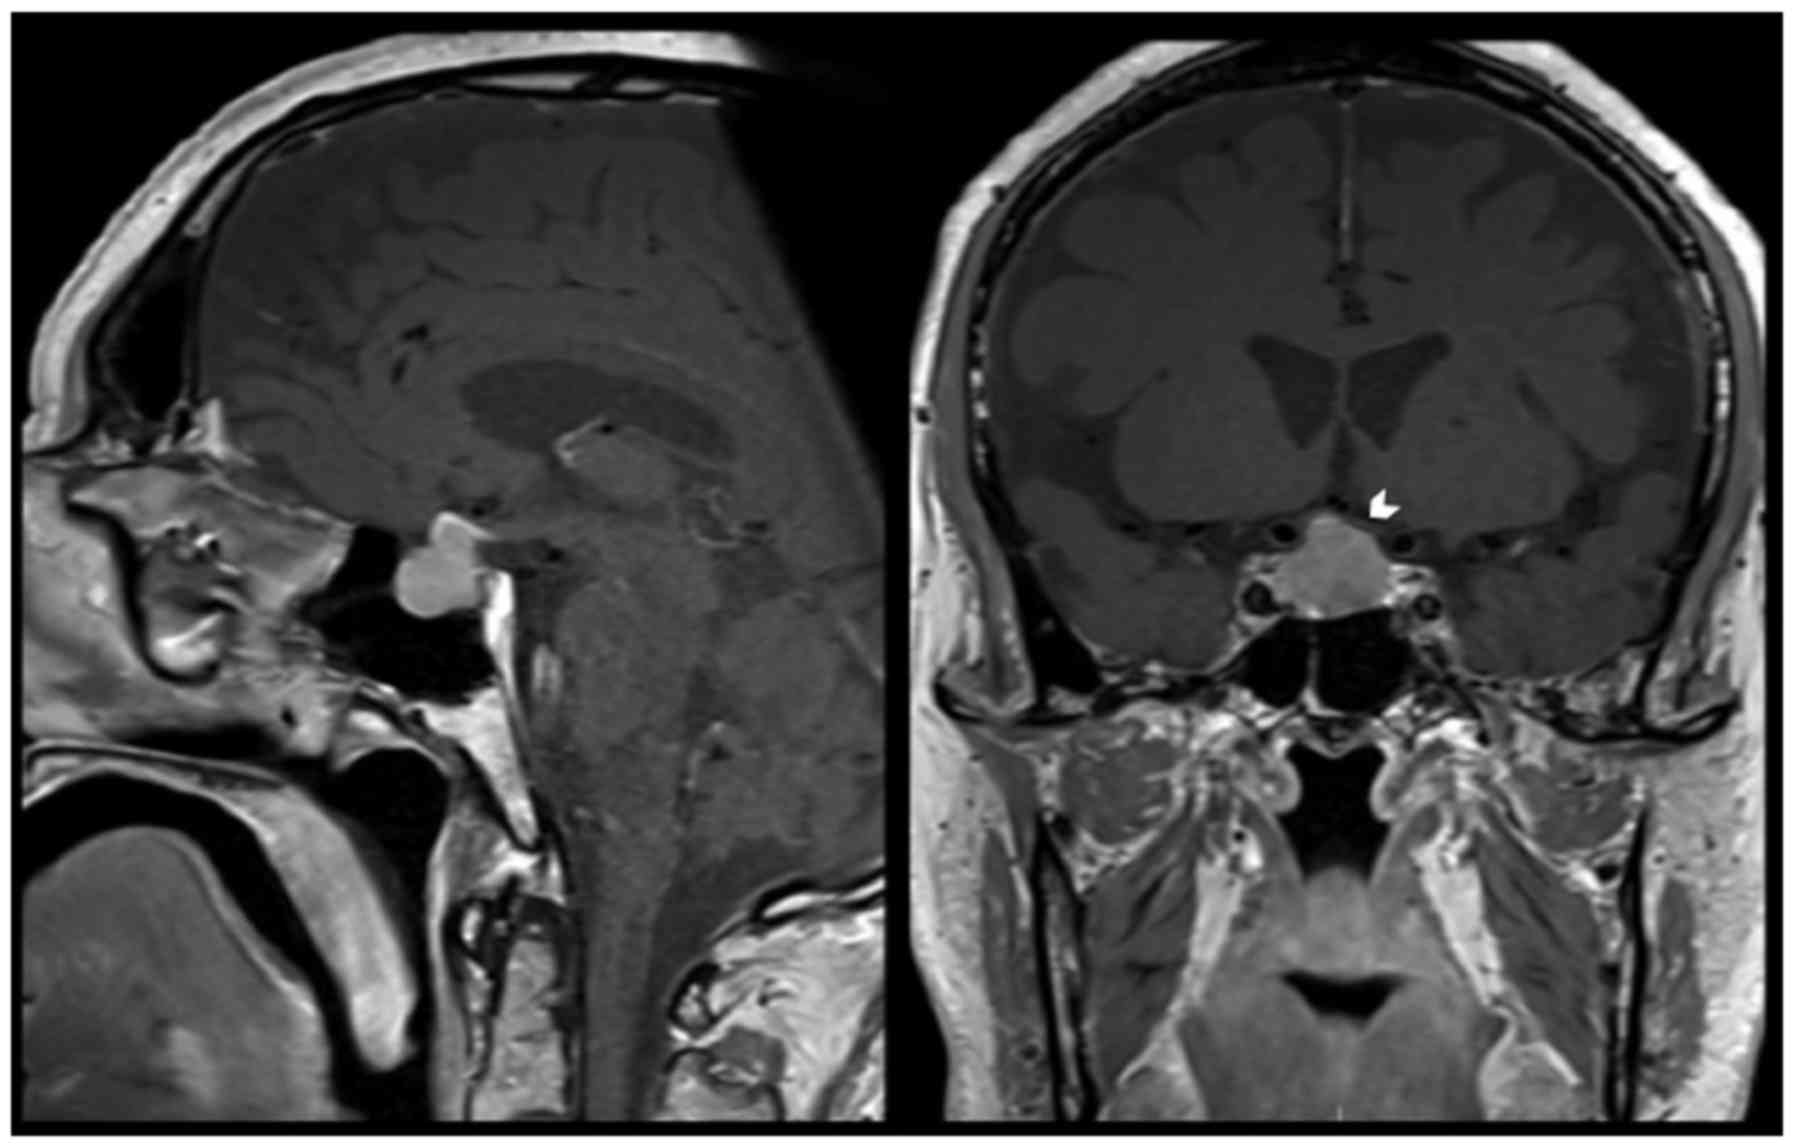

A 77-year-old man presented to the University Hospital of Lausanne in October 2015 with fatigue and clinical signs of hypogonadism. The clinical presentation was suggestive of hypopituitarism and endocrine tests showed an anterior pituitary dysfunction. Investigation with cerebral magnetic resonance imaging (MRI) demonstrated a sellar lesion with suprasellar extension and no compression of optic structures. He was admitted at the neurosurgical department and initial management consisted of hormonal replacement therapy and a ‘watch-and-wait’ approach. One year after his initial presentation (October 2016), the patient returned to the emergency department with a thunderclap headache. A cerebral MRI demonstrated pituitary apoplexy (Fig. 1). There were no visual deficits on clinical examination and we decided to continue the regular monitoring and follow-up. Over 6 weeks of follow-up the patient started complaining of visual symptoms, secondary to a progressive growth of the pituitary lesion with compression of the optic chiasm (Fig. 2). Ophthalmological examination confirmed a right temporal quadrantanopia.

Figure 2.

Sagittal (left panel) and coronal (right panel) views of a gadolinium enhanced T1-weighted cerebral magnetic resonance imaging revealing a sellar lesion with suprasellar extension, and intense homogeneous contrast enhancement. The pituitary stalk is not visible and the compression of the optic chiasm is evident (the left optic nerve is flattened just above the roof of the tumor and it is marked with an arrow head).